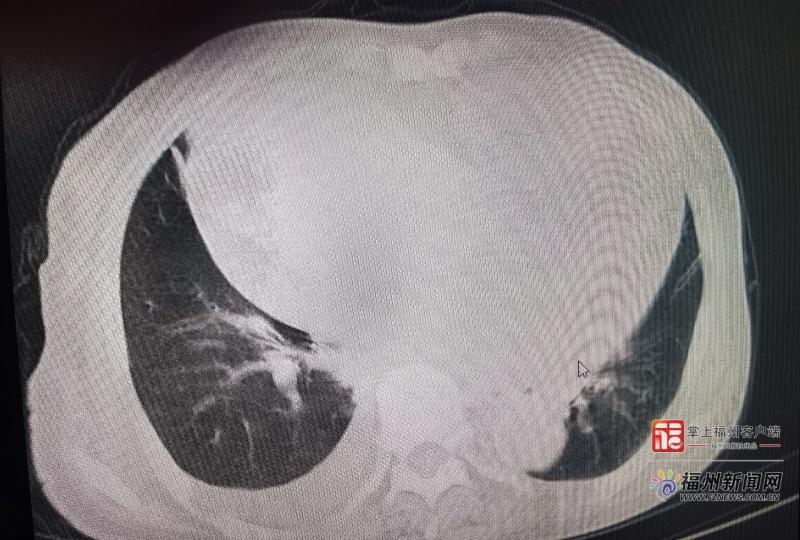

​老人不明原因乏力、食欲下降?专家提醒:这可能是无声警报患者影像图。(省老年医院 供图)

该院心血管内科主任医师王世红近日接诊一例78岁的老年女性。该患者术前评估时自称可上四层楼,无典型气促,仅偶有食欲不佳。但深入问诊发现,其上二楼即感双下肢无力,需休息后才能继续。后续检查证实其心脏已明显扩大且功能受损。“这位患者的主观‘正常’掩盖了客观的‘异常’。若非细致追问,极易漏诊。”王世红表示,临床上约40%的老年心衰患者常表现为两周以上不明原因乏力、食欲下降等非典型症状,若误认为是衰老而忽略检查,可能错失治疗良机。